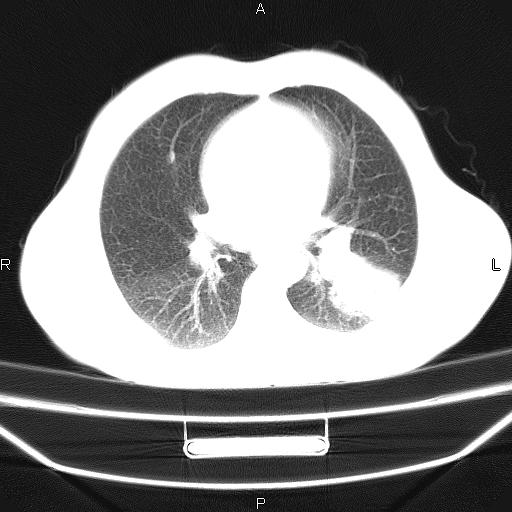

患者,男,40岁。间断发热,咳嗽二十余日。体温最高达38.9° 在当地诊所抗炎治疗三天后体温降至正常,患者自行停药。今又发热。胸片示,左下肺阴影。

左下肺片状高密度影,境界模糊,密度不均,考虑感染性病变可能性大,建议抗炎治疗后复查。左肺门增大,不除外占位性病变,必要时支气管镜检。